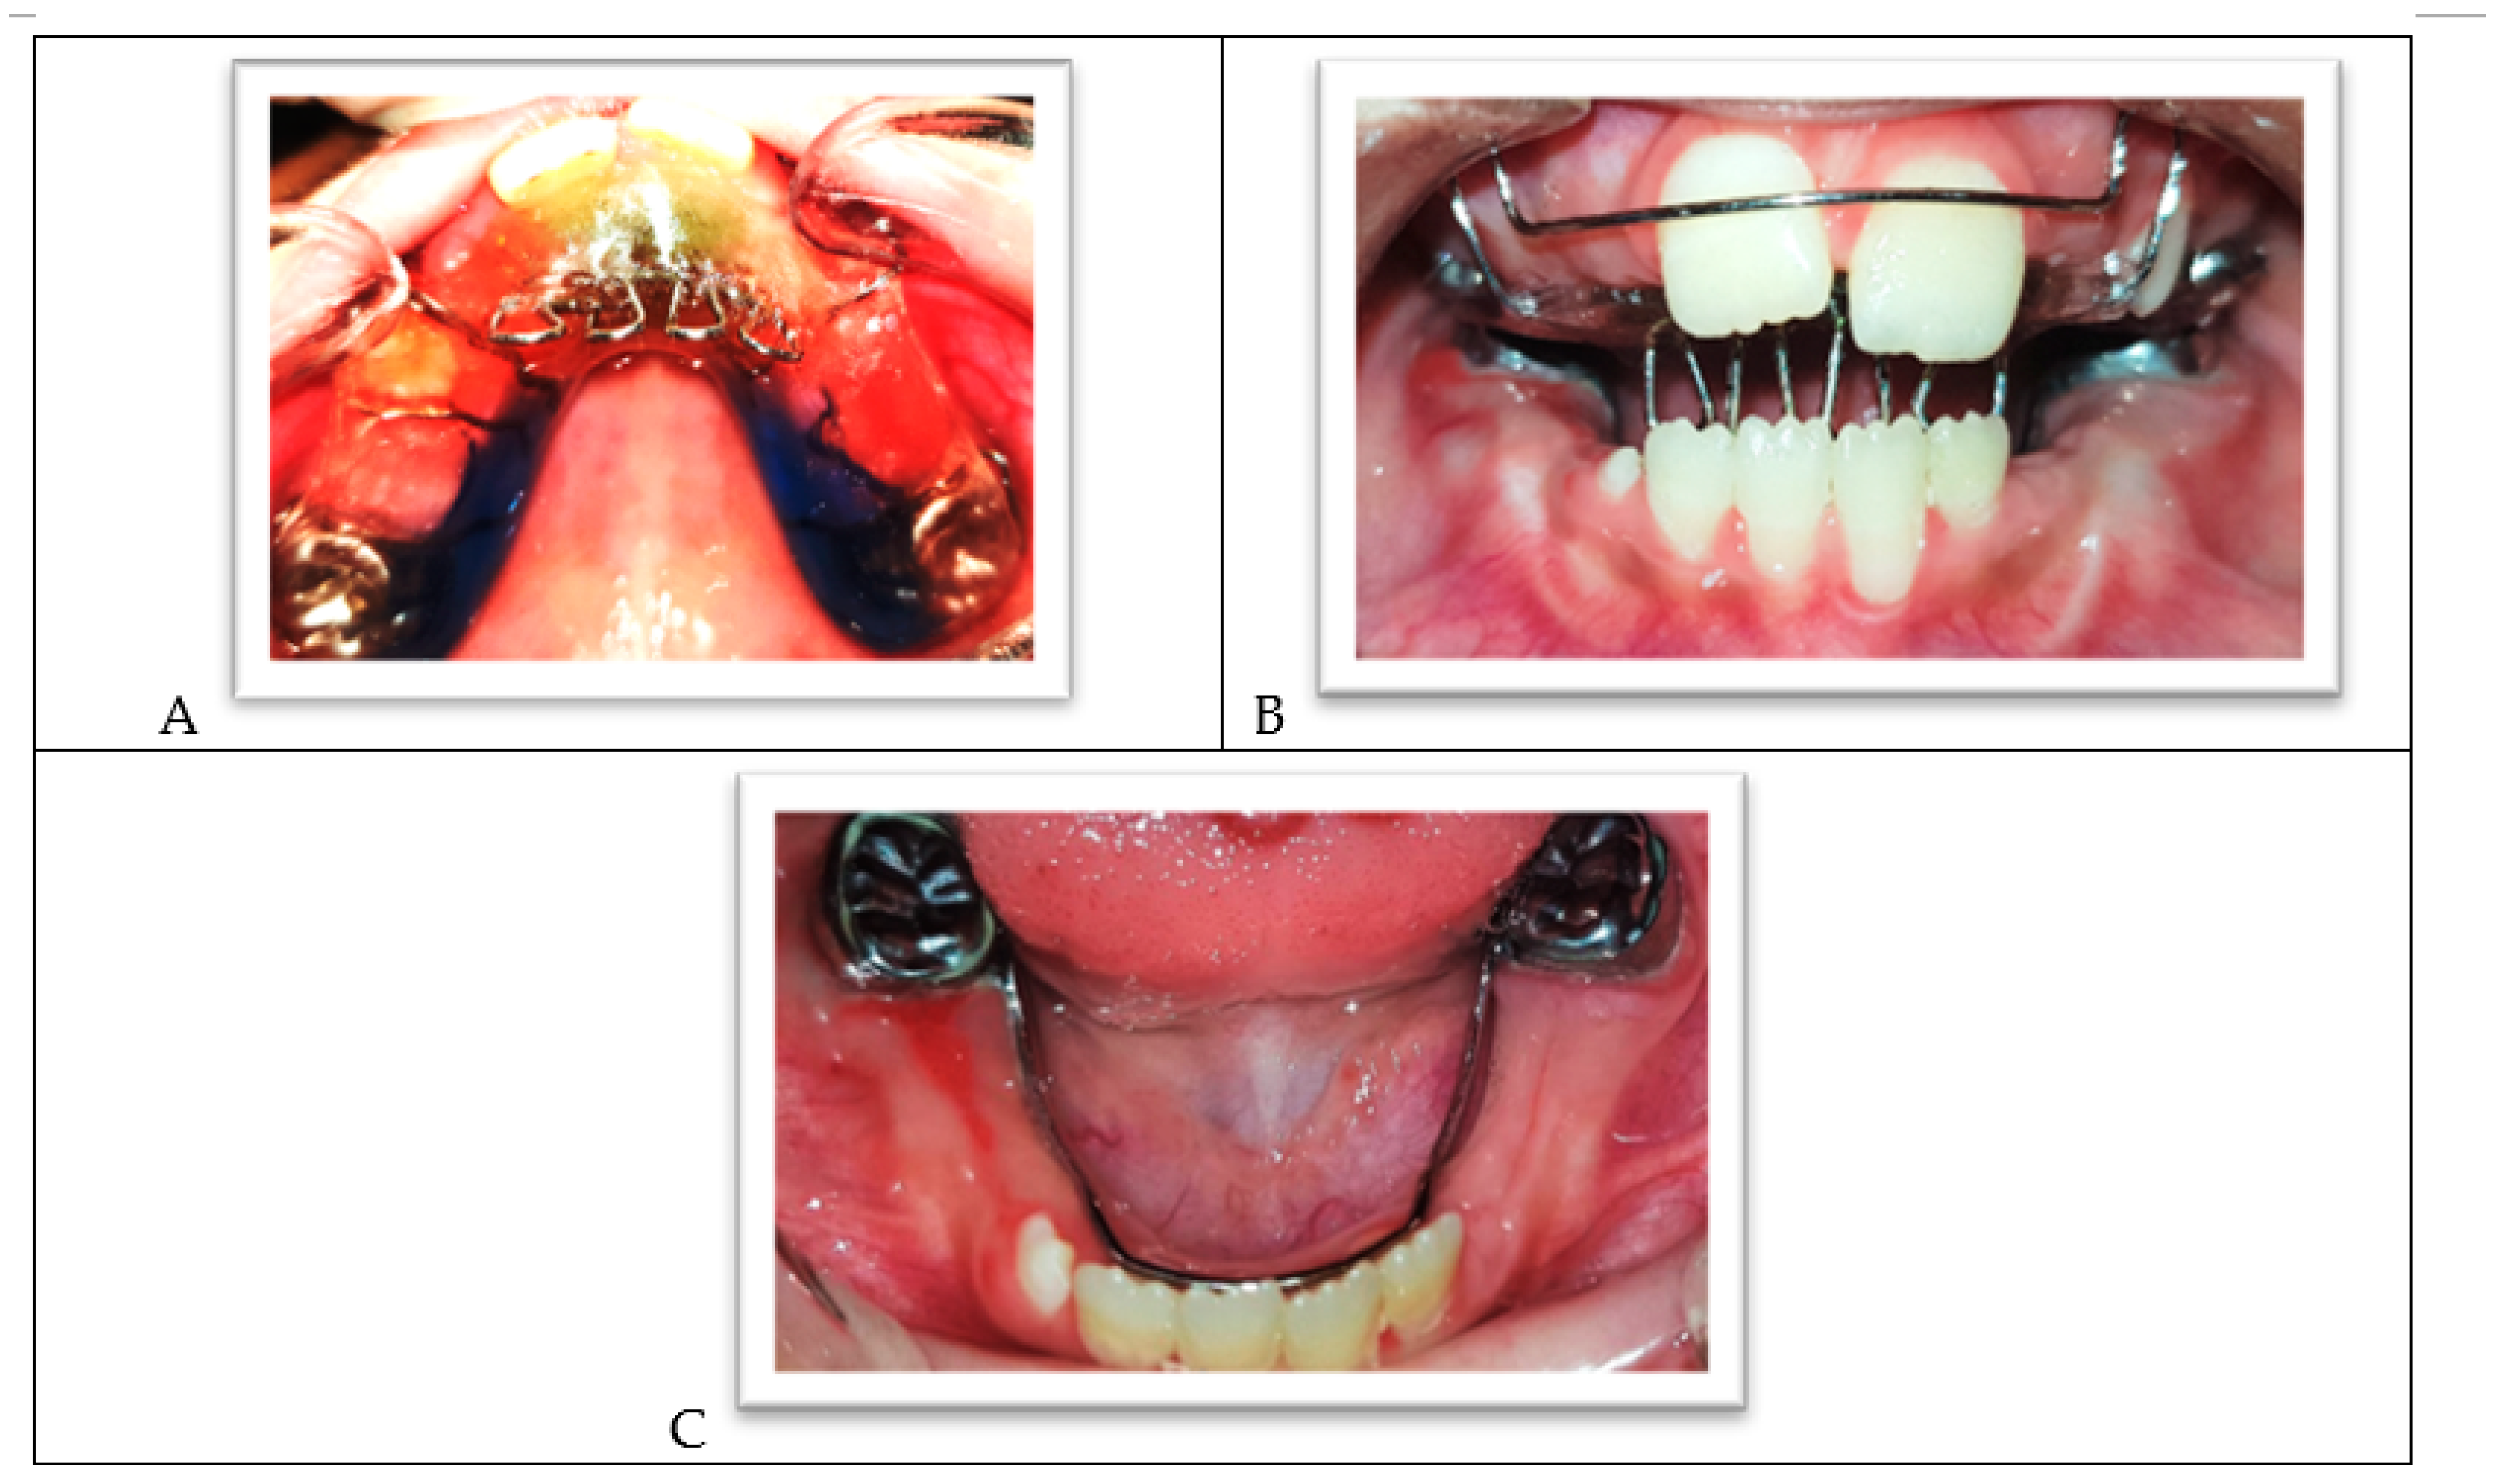

After all the dental treatments were performed, interceptive orthodontic treatment was planned to prevent finger sucking and tongue thrusting so that the anterior teeth could re-establish normal eruption and the space of the lower canines and premolars could be preserved. After discussing the advantages and disadvantages of this treatment with the parents, alginate impressions were taken of the child’s upper and lower jaws to make a removable palatal crib for the upper jaw and a fixed lingual arch for the lower.

In the next session, the palatal crib was placed (Figure 9A,B), and the lingual arch was cemented to the lower permanent molars crowns with a glass ionomer luting cement (Figure 9C). The child and parents were given instructions on cleaning and wearing the palatal crib, and oral hygiene was emphasized. The palatal crib was used for 11 months; it has been slightly modified to accommodate the emergence of the premolars.

Figure 9.

(A) The upper arch with a palatal crib. (B) The palatal crib in occlusion. (C) The lower arch with the lingual holding arch.